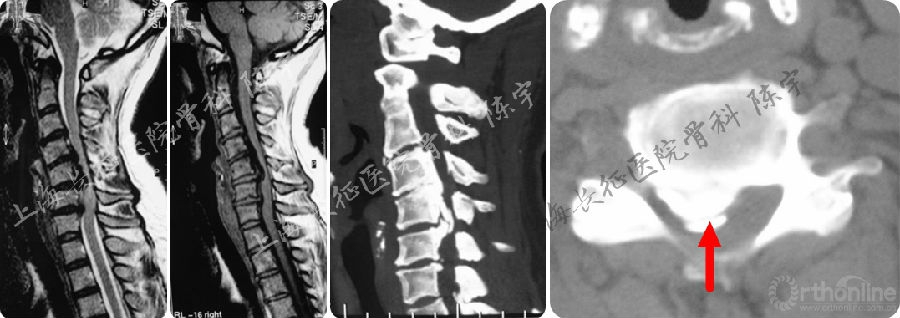

术前影像学检查(图1):

(1) X线:颈椎侧位及伸屈侧位片显示颈椎呈后凸畸形;

(2) MRI:颈4-6水平脊髓严重受压;

(3) CT: 颈4-6连续型后纵韧带骨化,在最严重水平椎管狭窄率达到90%以上,在横断面上表现为典型“双影征”,提示合并硬膜囊骨化。